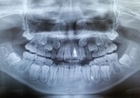

歯科医院では、歯の検査やレントゲン撮影が行われ、痛みの原因を特定します。その後、適切な治療法が提案されます。治療内容は、虫歯の治療や歯並びの調整、歯茎の炎症の治療などです。

歯科受診の際、まずはお子様の歯の状態を詳しく確認します。虫歯がないか、歯茎に炎症がないか、歯並びに問題がないかをチェックします。次に、レントゲン撮影を行い、目に見えない歯の問題がないかを確認することもあります。その後、必要に応じて治療を行います。例えば、虫歯が見つかった場合にはその治療、歯茎の炎症があれば抗炎症剤を使用した治療を行います。

さらに、定期的な検診や歯磨き指導を受けることで、予防ケアができ、今後の歯の健康維持に役立ちます。